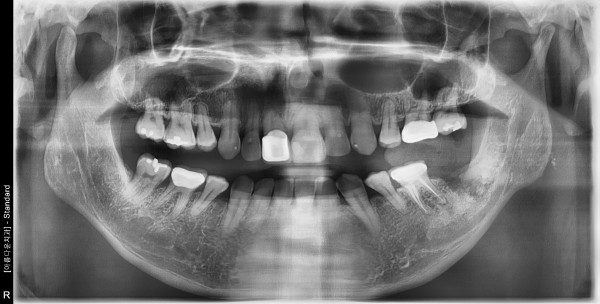

50세 남/ 하악 좌측 어금니 발치 및 치조골이식술 후 임플란트 식립